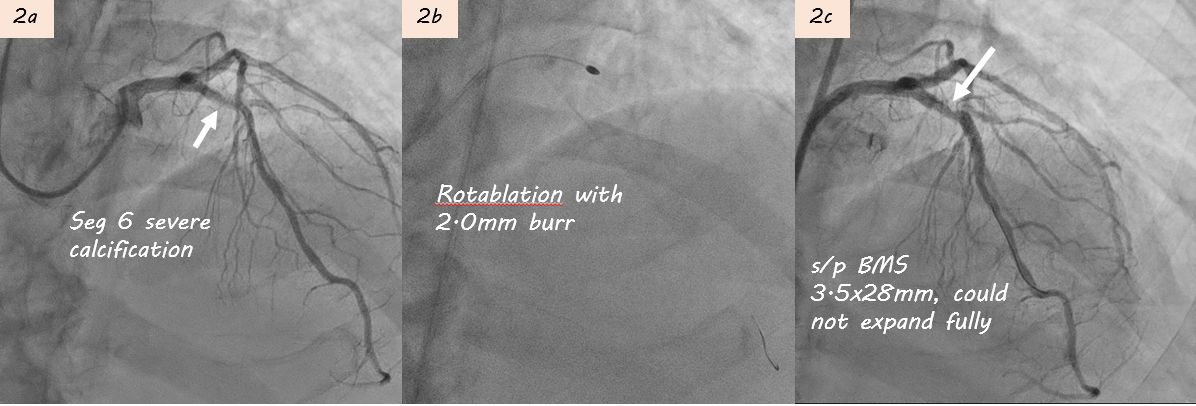

The first angiography revealed 2-vessel disease with 60% stenosis in RCA seg2 and 90% stenosis in LAD seg6. A 3.0¡¿20 mm Euphora balloon could not fully expand, and intravascular ultrasound (IVUS) confirmed heavy calcification. Rotational atherectomy using a 2.0 mm burr was performed, followed by implantation of a 3.5¡¿28 mm bare-metal stent (BMS) (Fig 2a-c). However, one week later, the patient developed STEMI, and repeat angiography showed subacute thrombosis within the LAD stent (Fig3).

During 1st PCI, IVUS showed severe calcification in LAD seg6 (Fig. 2a). Rotablation with a 2.0 mm burr was performed (Fig. 2b), and a 3.5¡¿28mm Multi-Link BMS was implanted but remained underexpanded (Fig. 2c).STEMI developed one week later prompted repeat CAG showing subacute thrombosis within LAD stent (Fig. 3a). Thrombus aspiration was performed. POBA with a 3.5¡¿15mm Raiden balloon (up to 24 atm) failed to fully expand the stent (Fig 3b). Subsequently, a 3.5¡¿30mm MagicTouch DCB was used.During 3rd PCI,rotational atherectomy was performed with 1.75mm and then 2.0mm burrs; however, 2.0 mm burr entrapment occurred during lesion crossing, and angiography showed limited debulking effect (Fig 4a-b). High-pressure balloon with APT NC 3.5x12mm were attempted but rupture(30 atm). We then POBA with Raiden 3.5¡¿15mm (30 atm), Raiden 4.0¡¿15 mm (32 atm), and NC Euphora 4.5¡¿15mm (20 atm). Finally, 4.0x40mm B. Braun DCB angioplasty was performed (Fig 4c).4th PCI was performed 1 month later for intravascular lithotripsy (IVL) and new stent implantation. Second time rotablation with a 1.75 mm burr was performed (Fig. 5a-b). IVL with a 4.0¡¿12mm balloon (100 pulses) achieved adequate expansion (Fig. 5c–d). Adequate POBA were followed by final stenting using a 4.0¡¿23mm Firehawk DES (Fig. 5e). Proximal optimization technique and kissing balloon technique were performed (Fig. 5f). Serial IVUS showed better debulking after 2nd Rotablation and IVL, and adequate new stent expansion (Fig 6a-6f).